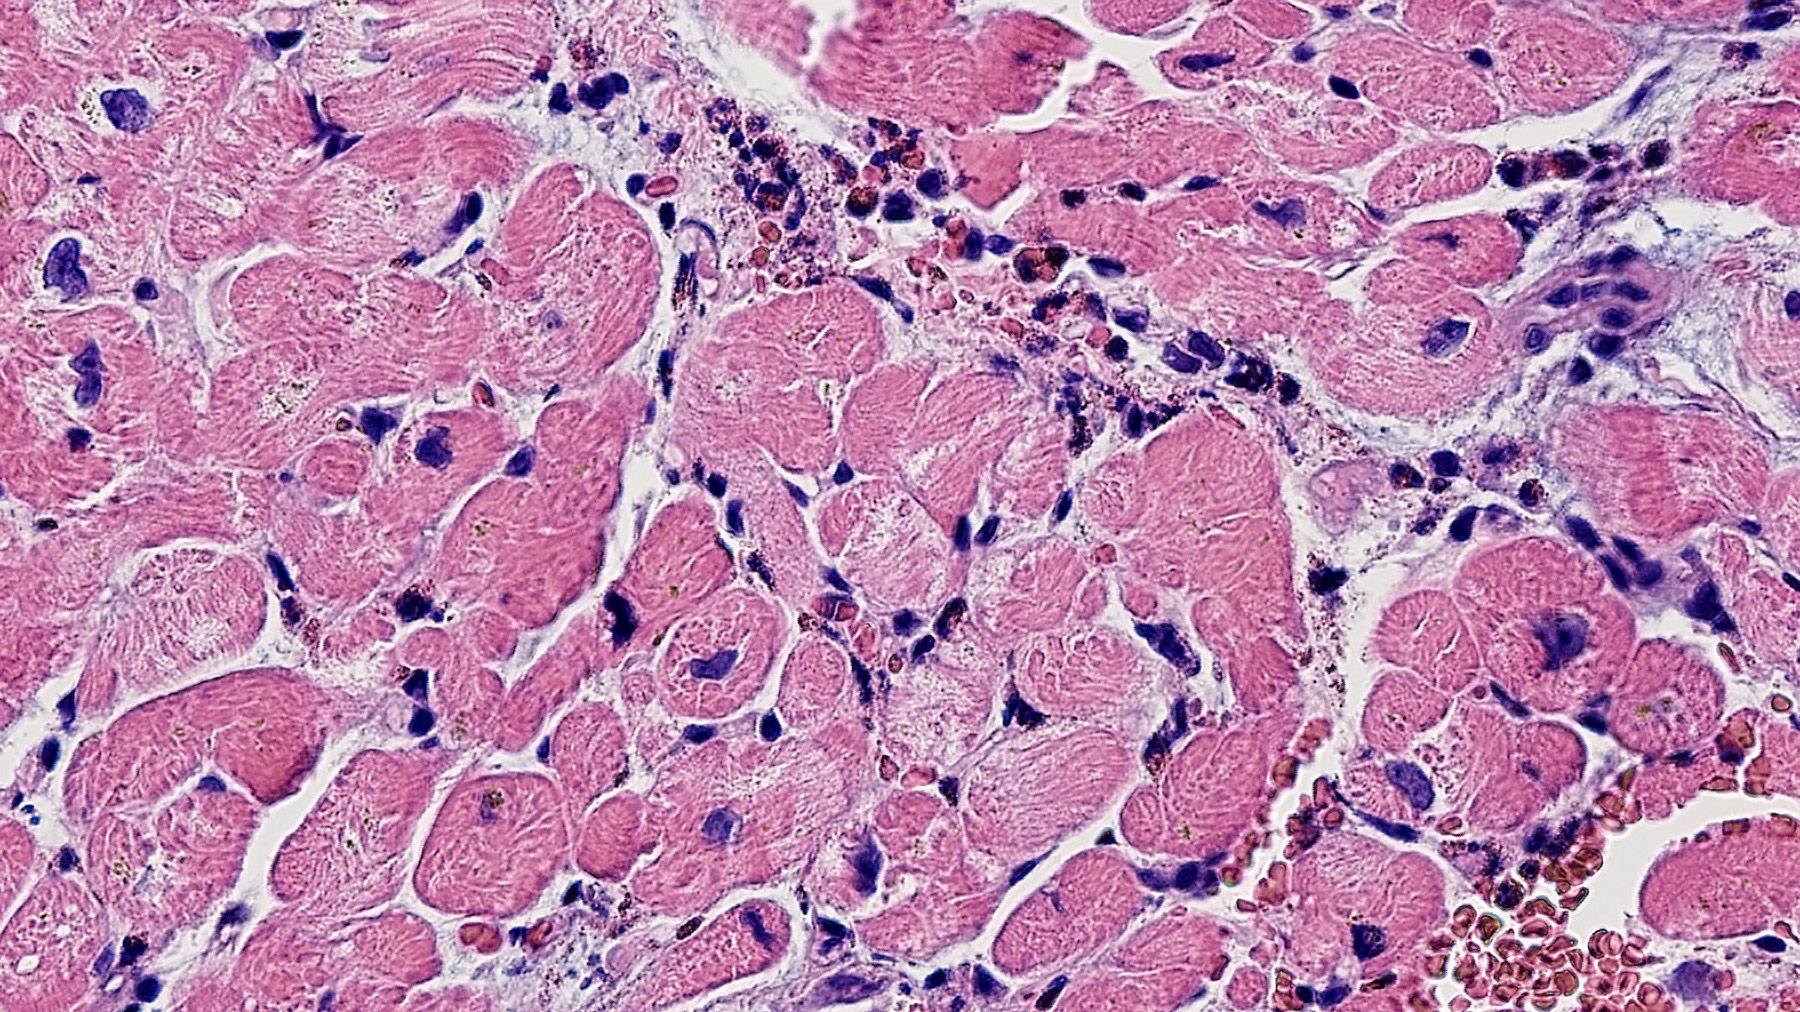

Clinical History: 33 year-old female with history of eosinophilic granulomatosis with polyangitis (Churg-Strauss syndrome) developed myocarditis.

Histology: H&E stains (Figures A, B) demonstrate myocardium with increased number of perivascular chronic inflammatory cells admixed with eosinophils, some clustered in micro-abscess lesions. Some scattered eosinophils are also present between the myocardial fibers (arrow in Figure B).